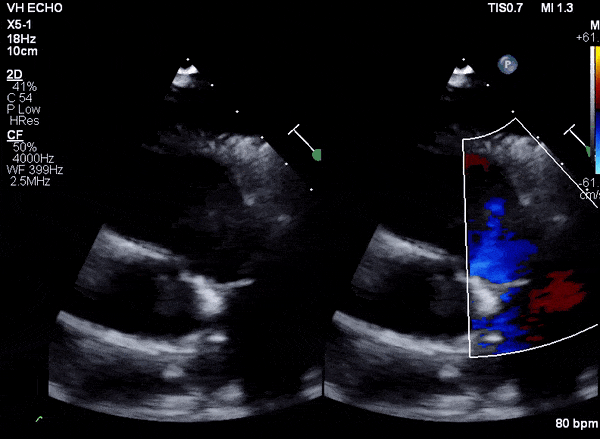

Transesophageal Images

Case 2 (Pulmonic Valve IE)